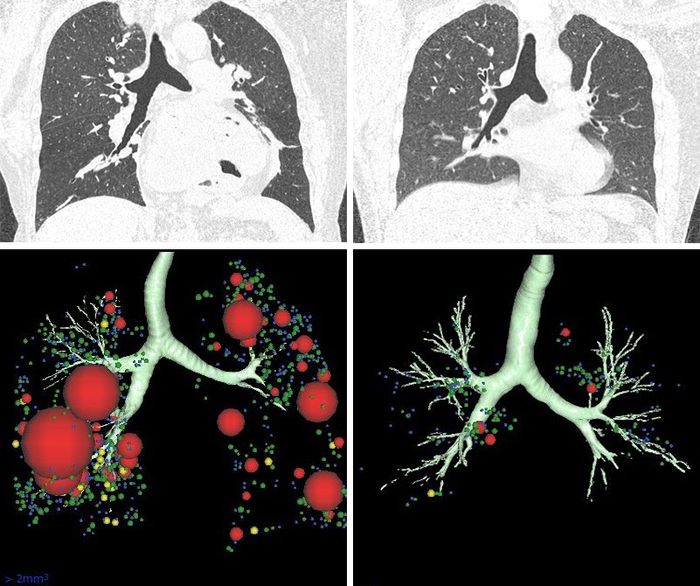

A novel CT scan-based approach has revealed significant changes in a parameter indicating lung destruction in some asthmatics. This finding could lead to more personalized treatments for asthma accompanied by persistent airflow limitation.

Shimizu and her colleagues applied a novel computer tomography (CT)-based approach to detect changes in lung tissue. In this approach, the scientists examined CT scans employing an index called “exponent D” for areas of reduced lung density with increasing coalescence of neighboring airspaces, which indicates emphysema, or the destruction of air sacs. The team also measured airway obstruction by testing the ability of people with asthma to forcefully exhale air in one second. This ability is reduced when the airways are narrower.

The researchers found that people with asthma who experienced persistent airflow limitation, regardless of the severity of their asthma or their smoking status, exhibited constricted airways and also showed signs of lung tissue destruction.

The changes to lung tissue on CT scans in this subgroup of asthmatic patients were not associated with the typical inflammatory markers linked to bronchial asthma. This is important, because it could explain why conventional anti-inflammatory treatments are not as successful in this group.